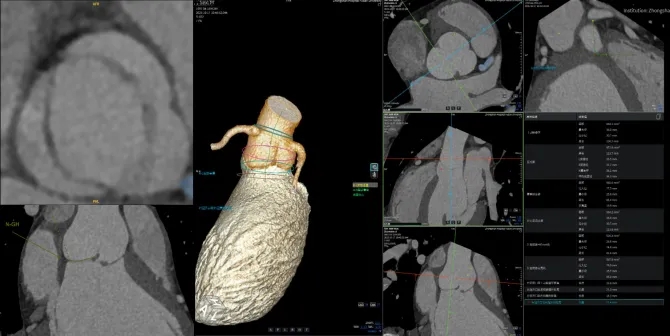

图:术前CTA评估主动脉瓣可修复性

首例直播病例(28 岁男性):发现心脏杂音9年,近1年出现活动后气促,影响正常生活。查体心率72次/分、律齐,胸骨左缘闻及 III/6 级舒张期杂音;心脏彩超提示极重度主动脉瓣关闭不全,主动脉窦部直径35mm、基底环直径28mm,LVEF67%、LVEDD58mm;术前 CTA 明确为二叶主动脉瓣(BAV),融合型 R-L,无冠瓣叶几何高度21.3mm,作为年轻患者,其核心诉求是规避终身抗凝与二次手术风险,保障长期生活质量。

病例 2(51 岁男性):体检时偶然发现 BAV 伴重度反流2周,无明显症状但心超示左室明显扩大已达到主动脉瓣反流手术指征。心脏彩超提示二叶主动脉瓣(BAV),融合型 R-L,重度反流,主动脉窦直径37mm、基底环直径30mm。中年患者对手术创伤、恢复速度要求高,希望在治疗疾病的同时,尽量减少对工作与家庭的影响。

王春生教授团队基于术前心脏超声(TTE)与计算机断层扫描血管造影(CTA)的精准数据,制定了以 “微创 + 精准修复” 为核心的手术方案,每一步均体现技术前沿性: